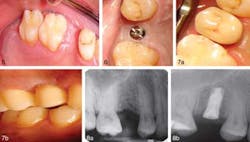

CASE 1Patient 1.Figure 1. Occlusal and lateral view before the procedure. Figure 2. Occlusal and lateral view of the direction indicator placed during the surgery showing minimal bleeding. Figure 3. (a) Occlusal view of the healing abutment in place immediately after implant insertion. (b). Lateral view of the direction indicator placed during the surgery. Figure 4. Digital periapical radiographic view before and after implant placement.